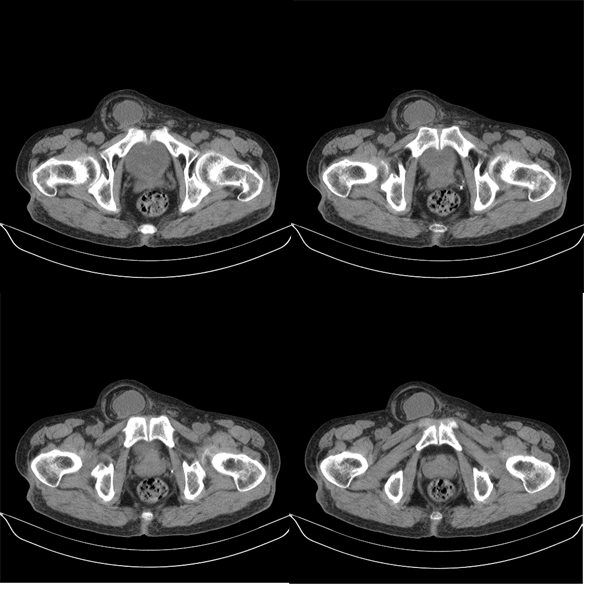

m79y自述30年前做过疝手术,20年前间断出现尿血,每次经抗炎治疗后即好转,近一月来又出现尿血但抗炎后仍尿血.现做双肾+盆腔ct:

双肾10mm扫描

该病人年龄过大故放弃了增强.ct做完后本人检查病人发现病人耻骨联合上稍偏右见一突出的包块影,质地柔软,平卧位手压后可以回缩.站立位突出明显!

膀胱三角区右侧可见较大软组织肿块,分叶状,内可见更低密度区,ct做完后本人检查病人发现病人耻骨联合上稍偏右见一突出的包块影,质地柔软,平卧位手压后可以回缩.站立位突出明显!考虑腹股沟斜疝,疝内容物为膀胱.膀胱内肿物考虑1炎性赘生物2平滑肌肉瘤(有多年血尿史,本次加重且抗炎不好转)3膀胱癌

1.膀胱内软组织肿快,有点状钙化,前列腺不大.膀胱癌.

2.右侧腹股沟斜疝。

3.双肾平扫未见异常.

1、右侧腹股沟斜疝,疝内容物为膀胱;2、膀胱右后壁肿块,考虑膀胱癌